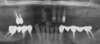

Avant traitement

Après traitement

Edenté total haut et bas

Mise en place de 6 implants en bas

Prothèse fixe vissée sur 6 implants